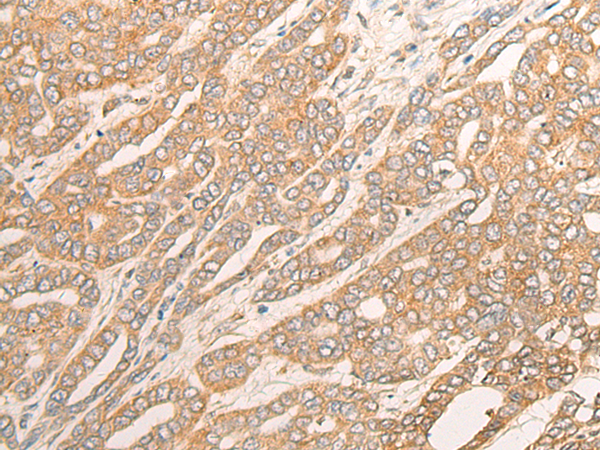

DCTD |

dCMP deaminase |

IHC Positive control: |

Human liver cancer; |

IHC Recommended dilution: |

25-100 |